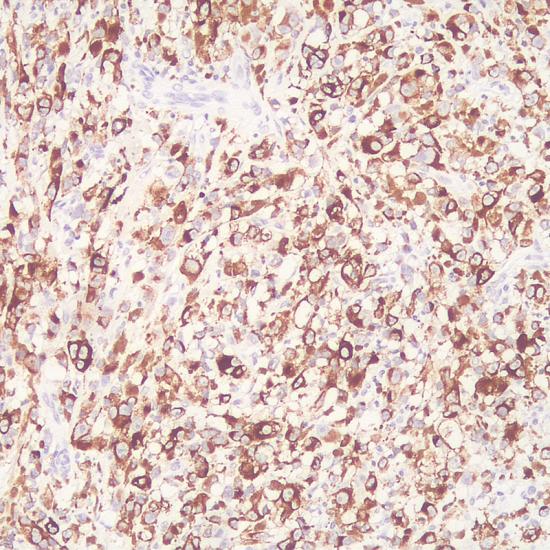

Melanoma

通過免疫組化的方法,該抗體可特異性識(shí)別存在于黑色素細(xì)胞和黑素瘤細(xì)胞中的一種蛋白。皮內(nèi)痣、正常成人黑色素細(xì)胞以及非黑色素性細(xì)胞不與之反應(yīng)。它與上皮、淋巴組織、神經(jīng)膠質(zhì)、間充質(zhì)起源的腫瘤細(xì)胞也不反應(yīng)。